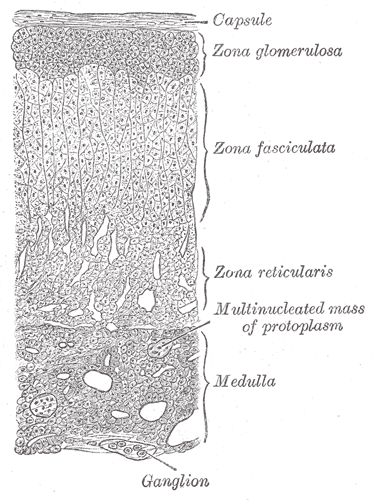

Adrenal Cortex

The largest and outermost portion of an adrenal gland is called the adrenal cortex.

The adrenal gland is composed of three distinct zones which include:

- Zona glomerulosa

- Zona fasciculata

- Zona reticularis

Zona glomerulosa produces mineralocorticoids like aldosterone.

Zona fasciculata creates glucocorticoids like cortisol.

Zona reticularis generates sex hormones like testosterone.

Adrenal Medulla

The adrenal medulla is the innermost part of your adrenal gland.

The adrenal medulla is the primary physiological source of catecholamines and are made up of neural crest-derived chromaffin cells.